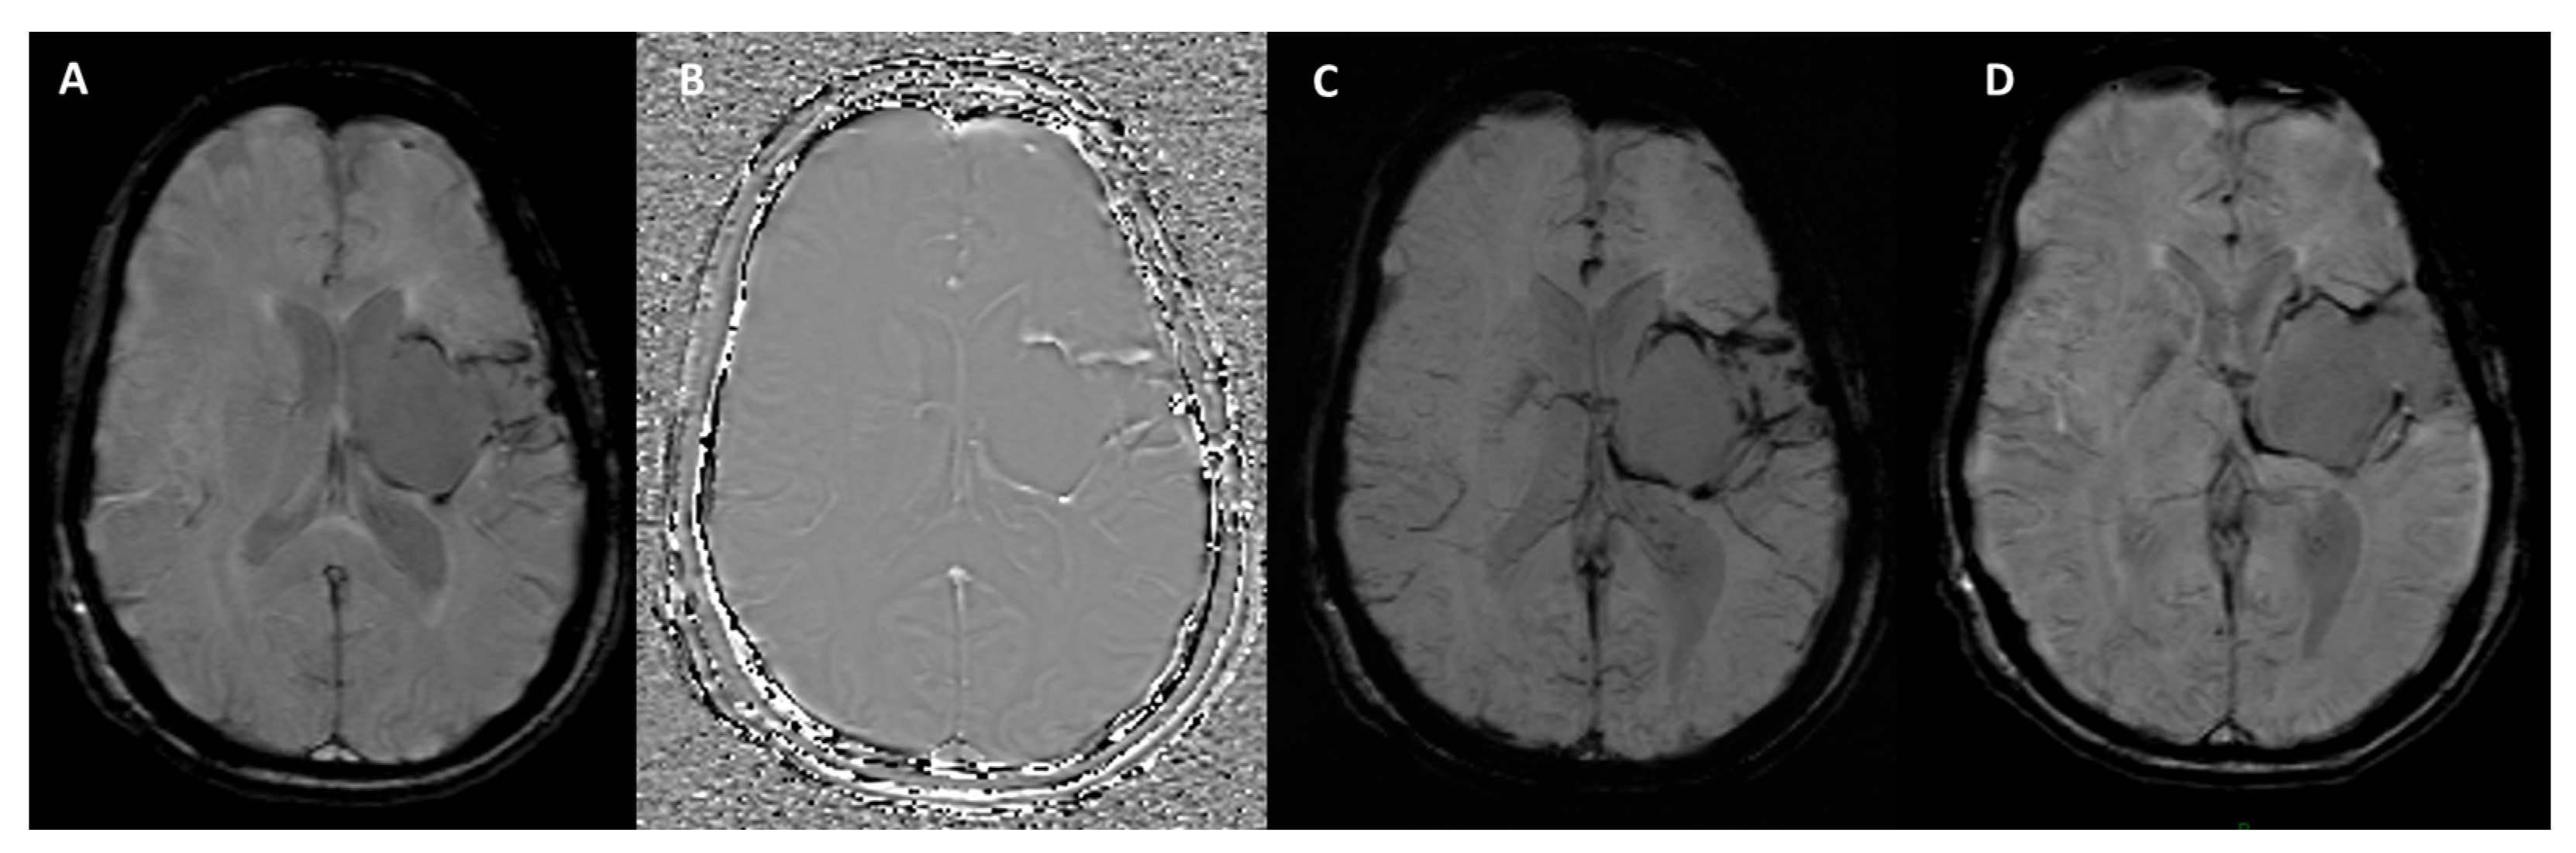

4.3. Cerebral Amyloid Angiopathy

4.4. Other Conditions